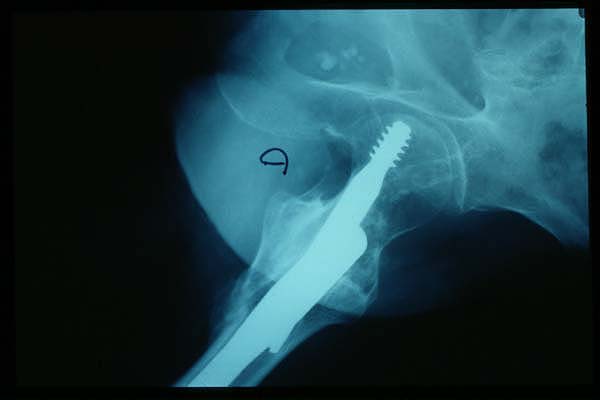

Fractura intertrocantérea de fémur, osteosíntesis